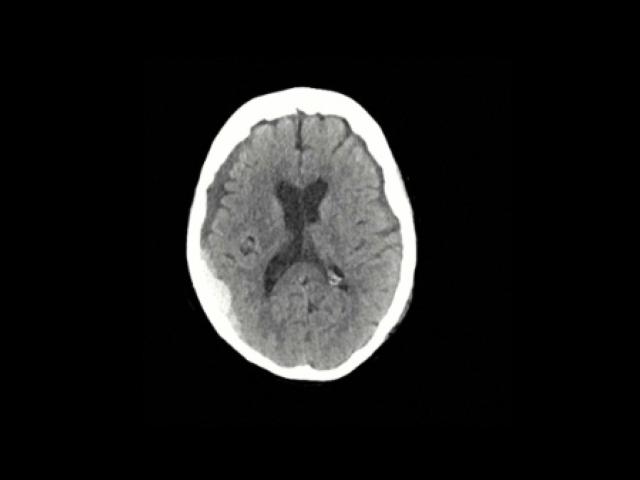

Sample Gallery